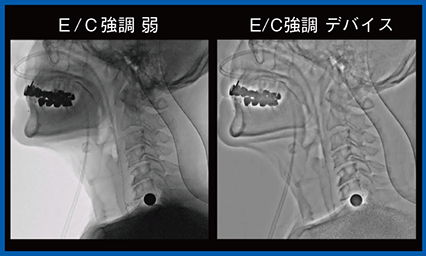

新画像処理条件Accentは,画像のコントラストと鮮鋭度を高め,デバイスの視認性を向上する機能である。標準透視のほか,画像のコントラストと鮮鋭度を高めるE/C強調(弱,中,強)と背景を圧縮するE/C強調デバイスがあり,透視を切らずに変更が可能なため,検査の状況に応じてスムーズな画質調整が可能である(図1)。

図1 Accentモード適用による視認性の向上(経気管支生検:TBLB)

強調を変えることで鉗子の視認性が向上している。